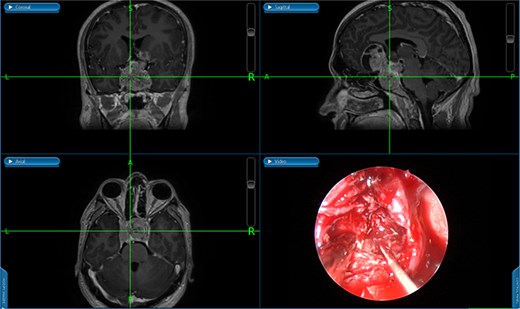

Despite treatment with cabergoline, follow-up prolactin level remained elevated, and imaging showed a growing tumor size. Clinically, the patient's symptoms persisted, with worsening headaches. Afterward, her prolactin level had dramatically risen to 2000 ng/ml. She was admitted with daily severe headaches, abdominal pain, vomiting, and oral intake intolerance. A brain MRI demonstrated an enlarged sellar and suprasellar mass measuring 3.2 × 1.7 × 3.0 cm, compressing the optic chiasm. Additionally, her prolactin level diminished to 2.7 ng/ml, raising concern of a growing pituitary macroadenoma.

She underwent endoscopic trans-sphenoidal debulking of the suprasellar lesion (Figs 3 and 4). Postoperatively, the patient developed complications, including diabetes insipidus and panhypopituitarism, requiring levothyroxine and corticosteroid replacement therapy. Histopathology revealed a diagnosis of high-grade primary central nervous system (CNS) B-cell lymphoma. Microscopic analysis showed sheets of atypical lymphoid cells with high mitotic activity. Consequently, the patient was initiated on rituximab and high-dose methotrexate (HD-MTX). Nevertheless, methotrexate was terminated due to the onset of acute kidney injury. Given the patient's intolerance to further HD-MTX, nivolumab was commenced based on PD-L1 expression. While there was partial symptom relief, the tumor response was inadequate. Therefore, the patient underwent whole-brain radiotherapy with a boost to the pituitary region, receiving a total dose of 45 Gy over 25 fractions. This treatment was effective, though she experienced alopecia, mild nausea, blurred vision, headaches, and severe vulvar itching.